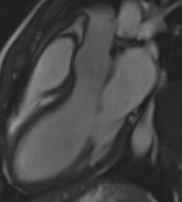

4 Chamber View